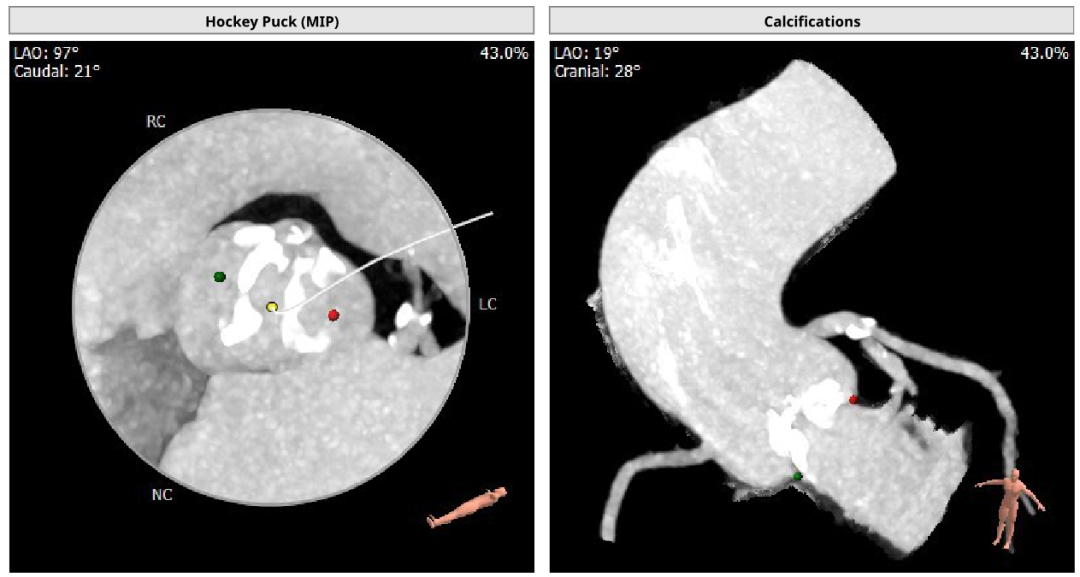

患者女性,77岁,Type 0二叶瓣。主动脉瓣重度狭窄,术前平均跨瓣压差80mmHg,峰值流速5.6m/s。瓣叶钙化,瓣环面积径21.1mm。左冠高度16.1mm,右冠高度16.0mm。外周入路可见钙化,内径尚可。

术中通过心内、心外联合高效协作,经右侧股动脉入路,使用17mm球囊预扩,成功植入21# RENATUS®球扩式经导管主动脉瓣,输送器顺利通过,瓣膜精准释放,术后即刻平均跨瓣压差由80mmHg降至8mmHg,术后峰值流速由5.6m/s降至2.0m/s。瓣膜释放位置理想、形态及功能良好,无外周血管损伤,术后无明显瓣中及瓣周反流等并发症。

术中造影